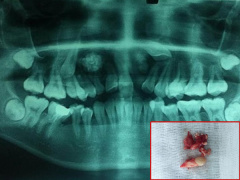

Con sưng miệng, bố mẹ đưa đi khám thì 'tá hỏa' khi bác sĩ lấy ra 526 chiếc răng trong miệng con

Sau khi chụp X-quang, các bác sĩ đã phát hiện hàng trăm vật thể lạ nhỏ li ti chen chúc trong khối sưng ở hàm bên phải của Ravindranath.

14 tuổi vẫn còn răng sữa, đi khám phát hiện u răng với hàng chục chiếc răng nhỏ

Một bé gái 14 tuổi, ở Hà Nội vì lý do lâu không thấy mọc răng đã đi khám tại khoa Răng Hàm Mặt, BVĐK Hà Đông. Các bác sĩ phát hiện bệnh nhân bị u răng 2 bên và kèm theo 2 răng ngầm nên đã chỉ định mổ lấy u răng.